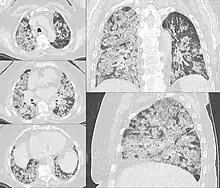

Recent hemorrhagic infarcts.

This commonly occurs when a distal pulmonary artery becomes occluded following a pulmonary embolism or other lung pathologies that can include malignancy, infection, or vasculitis. A large percentage (77%- 87%) of lung infarctions occur unilaterally, and typically in the lower lobes compared to the upper lobes. Symptoms of pulmonary infarction and pulmonary embolism are similar. Dyspnea, chest pain, pain and swelling in a lower extremity, and hemoptysis are common symptoms in both. Chest X-Ray can demonstrate a "Hampton's Hump" when pulmonary infarction is present, but Cat Scan is more commonly used. Treatment is dictated by the underlying cause of the pulmonary infarction which has a broad differential diagnosis that should be considered during treatment. The underlying cause will assist in a treatment plan to include level of care during initial management and the involvement of various specialists as pulmonary infarction can be deadly.[6]